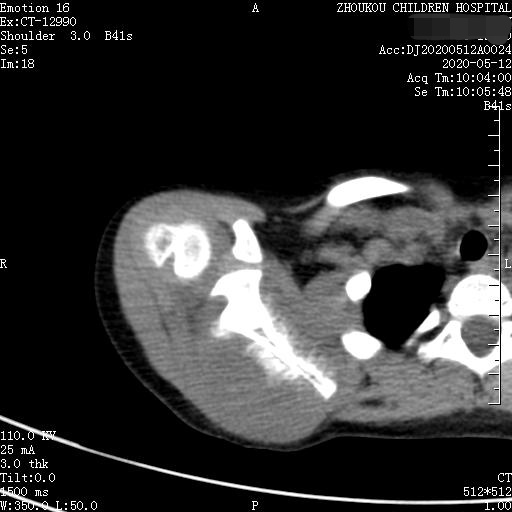

转移性骨肿瘤是最常见的恶性骨肿瘤,约占恶性骨肿瘤的75%。CT表现一般为溶骨型、成骨型、混合型。同一肿瘤的转移可表现为溶骨与成骨转移两种类型,同一病灶上可出现溶骨与成骨两种表现,少数转移灶呈囊状膨胀性破坏。脊柱的溶骨性转移累及附件并形成椎旁软组织肿块。前列腺癌、结肠癌、类癌的成骨性肋骨转移可表现为膨胀性硬化。前列腺癌容易转移到骨盆,鼻咽癌容易转移到脊柱。肾癌骨转移常为单发、溶骨性且呈多囊状或泡沫状,可伴有骨性房隔、局部膨胀性改变。颅骨溶骨性转移灶有时在溶骨区中央可见残留的正常骨或者密度增高骨,即常说的靶性病变。 术后随访家属得知:病人术后临床医生怀疑骨转移瘤(孩子过去有视网膜母细胞瘤一侧眼球摘除史)或神经外胚层性肿瘤?,建议基因方面检测。